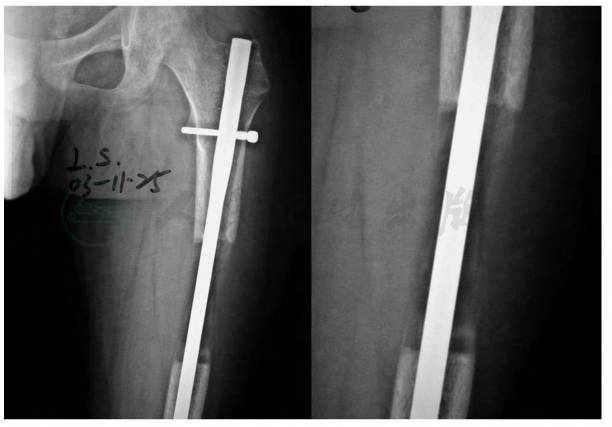

患者,男性,16岁。主因“右股骨外伤后骨折7年,短缩5年”入院。1996年8月14日因车祸致右股骨远端骨骺损伤,于当地医院急诊行清创、开放复位、斯氏针内固定术(图1)。术后伤口感染、骨骺损伤不愈合经多次清创术和术后换药伤口和骨骺损伤愈合。因自1998年开始发现双大腿不等长、跛行并进行性加重,于2003年7月2日至北京积水潭医院求治。既往体健。

图1 外伤术后片